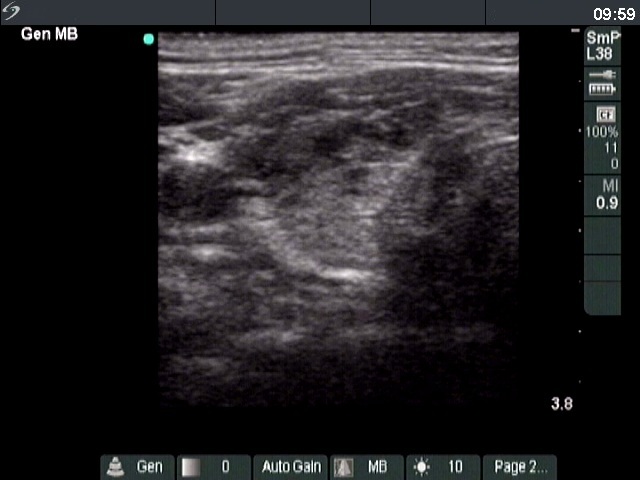

Ultrasonography. The thyroid was echonormal and presented several hypoechoic areas. The pattern in the right lobe was obviously focal form of lymphocytic thyroiditis.

A relatively large hypoechoic areas was found in the left lobe. The lesion had irregular borders. At first sight, this presentation of the left lobe could be interpreted as the central hypoechoic area-type form of lymphocytic thyroiditis. However, the hypoechoic lesion was not entirely surrounded with echonormal thyroid tissue. More importantly, the central hypoechoic areas-type form is almost always bilateral.

The sonographic pattern is remarkable. On the one hand, the tumor was identical to other more active foci of Hashimoto's thyroiditis. The only difference was the size of this lesion which was larger than other lesions observed in the thyroid. In the case of Hashimoto's thyroiditis neither the irregularity of border, nor the increased vascularization has any relevance. On the other hand, the tumor had microcalcifications and was significantly larger than other foci. The lesson to draw is the comparison of various lesions: if we detect a lesion which differs from others regarding the echogenicity, the size or the vascularization, it is advisable to perform FNA.